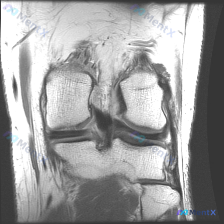

提供的单张膝关节MRI T1冠状位图像分析结果如下:

- 骨骼结构:股骨远端、胫骨近端、腓骨近端轮廓清晰,骨髓信号正常,未见局灶性骨质破坏或异常信号

- 关节软骨:股骨髁、胫骨平台表面软骨轮廓平整,无明显局灶性缺失或变薄

- 半月板:内外侧半月板均为结构完整、轮廓清晰的均匀低信号三角形影,内部未见信号增高影贯穿关节面

- 韧带结构:可见部分交叉韧带走行连续,无明确中断或异常增粗,侧副韧带区域软组织无异常

- 关节间隙与软组织:关节间隙宽度正常,无明显异常积液或滑膜增生,周围皮下脂肪、肌肉信号正常